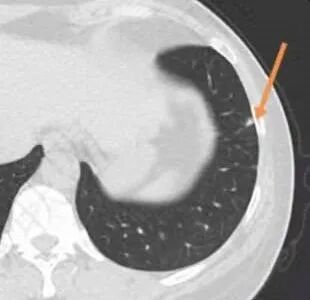

右肺尖可见混合磨玻璃结节影,边缘清晰,病灶比较散,多结节堆积感,近胸膜侧可见条索及卫星灶,考虑结核,鉴别腺癌

影像特点:右肺上叶混合磨玻璃影,边界清晰,结构松散,内有多结节堆积及支气管扩张影,可见小叶间隔增厚,并局部增厚的小叶间隔上亦存在微结节,胸膜侧可见纤细索条,病灶周围可见多发微结节影。

总体分析:从病灶分布来看符合结核的好发位置,影像表现也符合结核的多态性,且出现卫星灶。由于有边界清晰的GGO,需要鉴别腺癌,虽然此病例有边界清晰的GGO,但是它的GGO的边缘有结节感,呈多结节堆积,而腺癌的GGO缺乏这种“多结节堆积感”,另外,此病例也没有发现腺癌的胸膜凹陷征、毛刺征及月牙铲等。